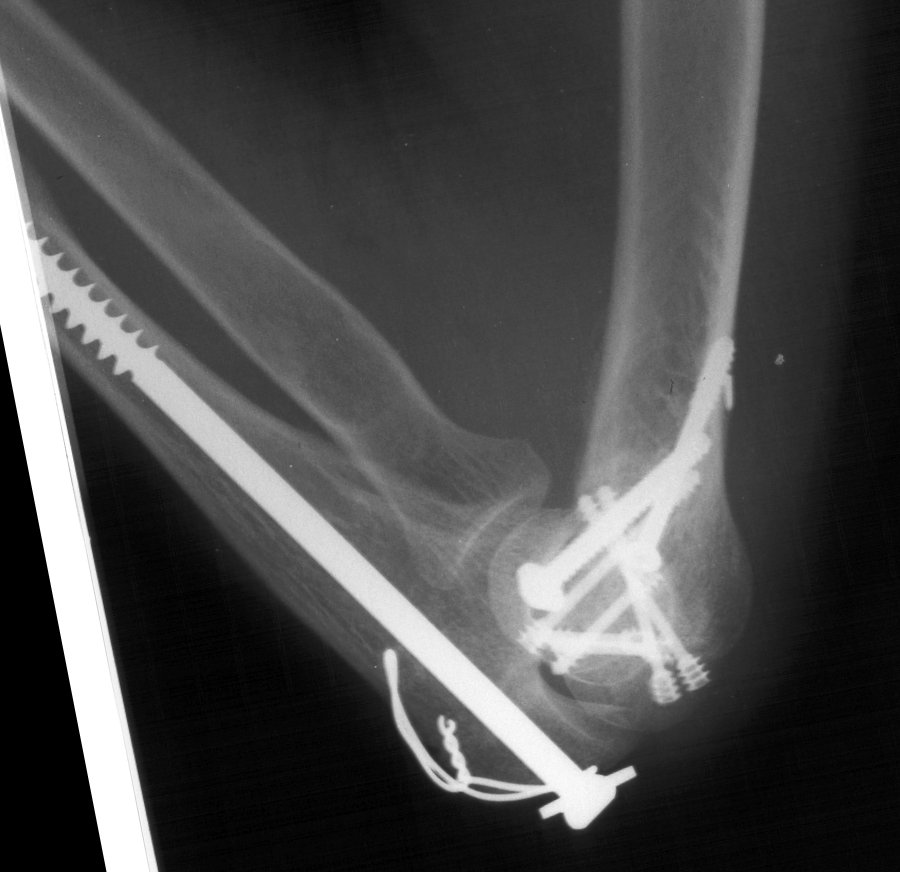

Transverse fractures of the condyles of the humerus or femur in which the fracture line crosses the fossae. Search to find out more about transcondylar fracture Here we look at the common humeral fractures can be classified into three types, depending on which part of the bone is broken.

Transcondylar fracture information including symptoms, causes, diseases, symptoms, treatments, and other medical and health issues. Vascular injury target population background. Transcondylar fracture information including symptoms, causes, diseases, symptoms, treatments, and other medical and health issues. Header codes like s42.47 require more digits to indicate the appropriate level of specificity. Management of supracondylar humerus fractures in children: Common fracture treated by pediatric common elbow fracture in young children. Low transcondylar fractures of the distal humerus in adults is rarely seen and reported in literatures. Here we look at the common humeral fractures can be classified into three types, depending on which part of the bone is broken. Specific coding for transcondylar fracture of humerus. Anatomy of the distal humerus includes medial and lateral columns. Transcondylar humerus with capitulum fracture is a relatively rare elbow. Anatomic reduction, rigid fixation and early motion are desirable. Supracondylar fractures of the distal humerus. It has a bimodal distribution in terms of age, affecting the elderly and younger patients. Transverse fractures may be amenable to column screws. There are several types of humerus fractures, depending on the location of the break. A humerus fracture is a break in the large bone of your upper arm.